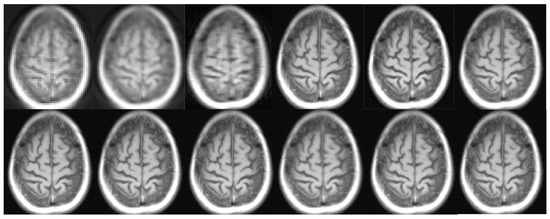

Figure 8. The subsequent depiction presents a clinical trial. The current study focuses on the reconstruction of an image using various techniques. In the first row, the regular sampling scheme is utilized without motion correction and SRR applied (1) (PSNR = 20.16 dB). The reconstruction process involves the use of a B-spline curve (2) (PSNR = 23.21 dB), Yang’s method [50] (3) (PSNR = 26.36 dB), Lim’s method (4) (PSNR = 29.11 dB) as referenced in [20], Zhang’s procedure (5) (PSNR = 28.71 dB) as referenced in [51], and Zhang’s second algorithm (6) (PSNR = 29.75 dB) as referenced in [43]. In the second row, Mahapatra’s method [52] (7) (PSNR = 30.03 dB) and Wang et al.’s procedure (8) (PSNR = 30.00 dB) are employed [53]. Furthermore, the reconstruction procedure utilizes Guerreiro’s et al.’s approach [54] (9) (PSNR = 30.03 dB), Pham et al.’s method [55] (10) (PSNR = 31.41 dB), Shi’s method [17] (11) (PSNR = 31.66 dB), as well as the author’s method (12) (PSNR = 32.99 dB) [20]. In addition, a sampling strategy and motion correction techniques are employed in order to achieve the super-resolution objectives. The aforementioned procedures are implemented without the inclusion of supplementary data. The compression ratio is 50%.